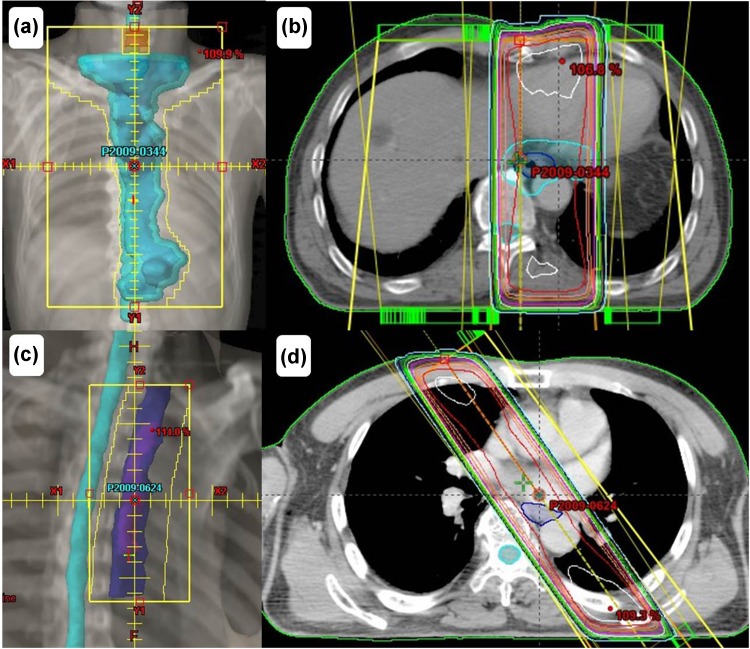

Fig. 2.

The initial field of this case is shown in (a) and (b), and the boost field of this case is shown in (c) and (d)

A 72-year-old man visited our hospital owing to an esophageal tumor. Blood tests performed prior to treatment revealed no liver or kidney dysfunction. His cardiac function was within the normal range. Upper endoscopic examination (Fig. 1a) revealed a type 4 tumor, diagnosed as squamous cell carcinoma by endoscopic biopsy. He was diagnosed with clinical T2N0M0 Stage IB [Union for International Cancer Control (UICC), 7th edition] esophageal cancer. Results from his blood and biochemical examinations are shown in Table 1. He was treated with concurrent CRT. Chemotherapy comprised two courses of slow infusion of 5-fluorouracil (5-FU), 400 mg/m2/day on days 1–5 and 8–12, and 2-h infusion of cisplatin, 40 mg/m2 on days 1 and 8 [3]. Before the second cycle of chemotherapy, Grade 2 leucopenia (CTCAE; common toxicity criteria for adverse events version 4.03 [4]) was observed, and the second cycle of chemotherapy was delayed by 2 weeks before being administered at the usual dosage. Concurrent radiotherapy of 60 Gy (30 fractions of 2 Gy, 5 days/week) was delivered over 9 weeks including a 3-week break. The initial target volume included the gross tumor volume and supraclavicular, mediastinal, and celiac axis lymph node regions until 40 Gy had been administered, and then only the gross tumor volume was irradiated, with care taken to avoid the spinal cord. The initial field of this case is shown in Fig. 2a, b. An additional 20 Gy boost dose was delivered, and the boost field is shown in Fig. 2c, d [5]. The dose volume histograms for this case are shown in Fig. 3, and the mean doses to the lungs and heart were 7.7 and 27.6 Gy, respectively. Thirty-eight days after the entire course of CRT, esophagoscopy was performed but it did not reveal the tumor and the inside of the esophagus was smooth (Fig. 1b). No malignant findings were observed on biopsy from the esophagus where the carcinoma had been located; thus, we considered this a complete response (CR).